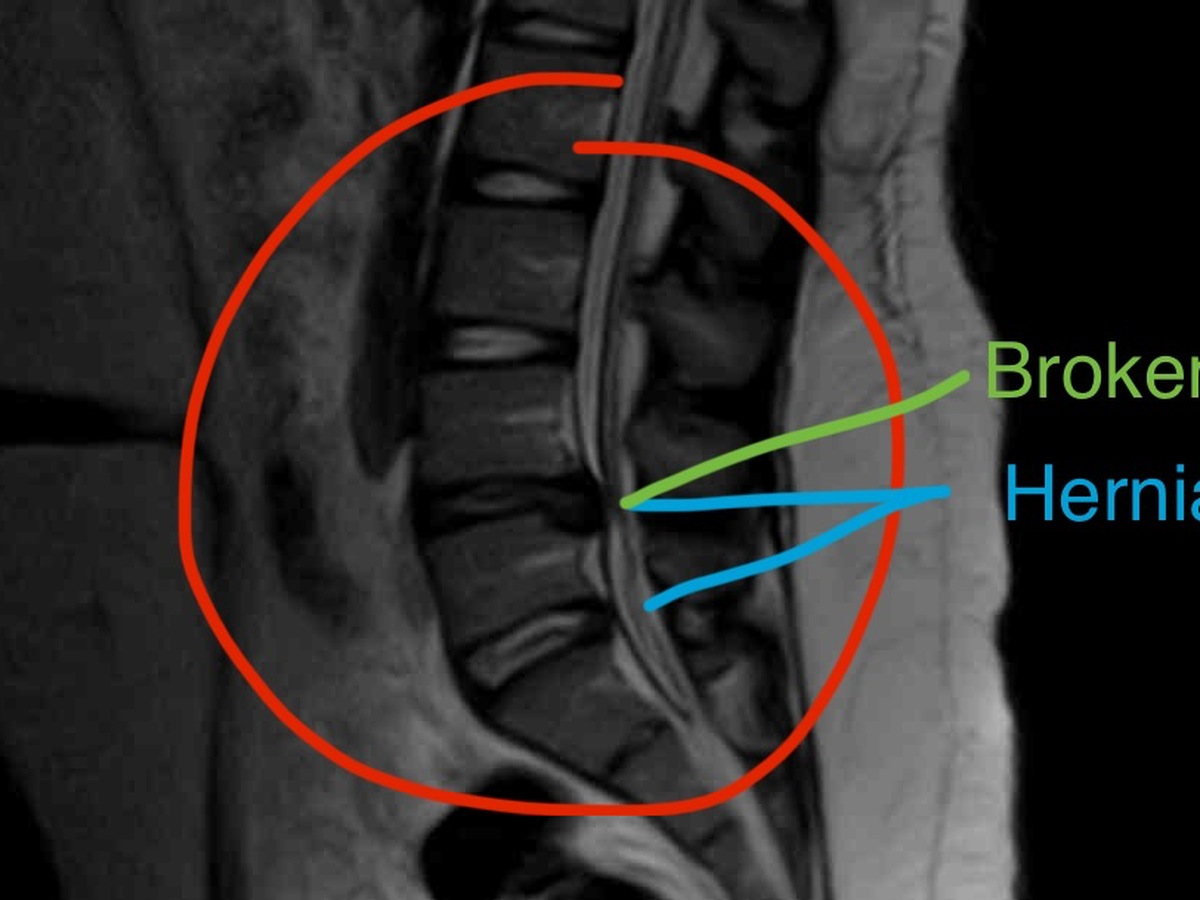

Needing help with medical costs after being hospitalized! While volunteering, Lake sustained a back injury that later became severe. She tried resting for a few weeks, thinking it was just a pulled muscle. During this time, she developed a kidney infection that progressed into the early stages of sepsis, making the pain unbearable. After going to the hospital for treatment, things only got worse. Although the kidney infection had been treated, the back pain hadn't gone away and was starting to spread to Lake's legs. After going back to the hospital for an MRI, we found out that she had two herniated discs in her back, one of them having been broken. With how bad the broken disc had gotten, an emergency surgery was imminent.